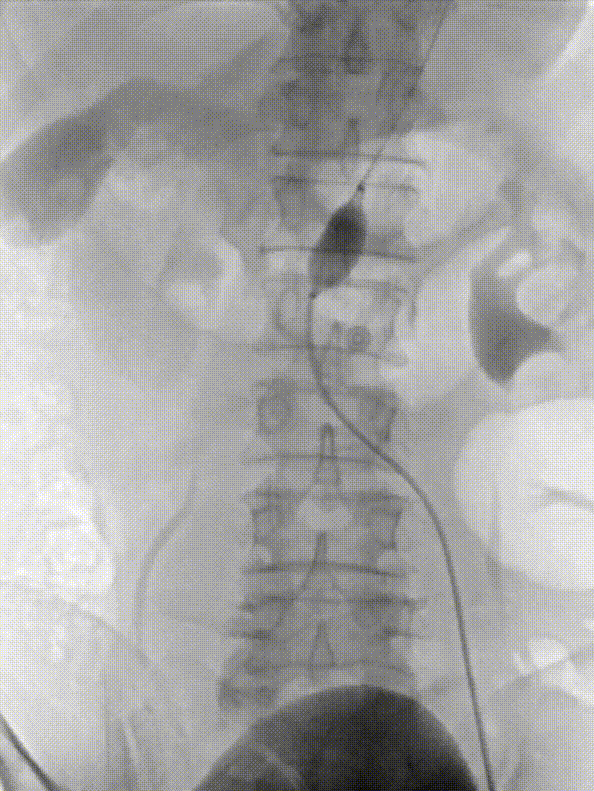

2. 经左侧股动脉入路,建立至降主动脉的输送通道,交换导丝,送入MOB球囊,将球囊位置推送至肾动脉以下,充盈球囊,阻断血流。

4. 穿刺左桡动脉,经左锁骨下动脉通过,输送导丝及椎管,输送至球囊近端附近,造影确认肾动脉位置。

gore医疗怎么样「漫腹精论」髂合时宜 精益求精——双MOB球囊导管辅助腹主动脉覆膜支架急诊治疗破裂巨大髂动脉瘤_https://www.jmylbn.com_新闻资讯_第15张